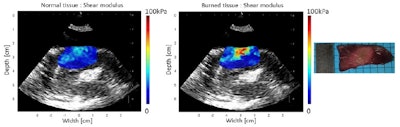

Shear modulus maps of the left ventricle, before (left) and after (center) ablation, with SWE and HIFU performed through an esophagus. The mean shear modulus increased from 21.2 ± 3.3 kPa to 73.8 ± 13.9 kPa in the central-8-mm-diameter zone. A photograph of the gross pathology section is shown on the right.

In an example ablated zone in the chicken breast, the mean shear modulus increased from 4.8 ± 1.1 kPa before ablation to 20.5 ± 10.0 kPa after treatment. In the left atrium, the mean shear modulus increased from 12.2 ± 4.3 to 30.3 ± 10.3 after ablation. In one of the left ventricle ablations, the researchers inserted an ex vivo esophagus around the transducers and performed HIFU and imaging through the esophagus. Here, the mean stiffness increased from 21.2 ± 3.3 to 73.8 ± 13.9 kPa in the central region.

Before and after ablation, the researchers used the probe to record a B-mode ultrasound image and perform SWE mapping. Shear modulus maps recorded before and after HIFU ablation showed clear changes, with thermal lesions clearly seen on all postablation stiffness maps. In contrast, B-mode ultrasound imaging was unable to visualize the thermal lesions.

"SWE provides reliable and precise ablation extension maps," Kwiecinski said. "The link between increased tissue stiffness and thermal coagulation, combined with a high specificity, has been shown. B-mode ultrasound only provides images with very poor specificity and poor contrast."